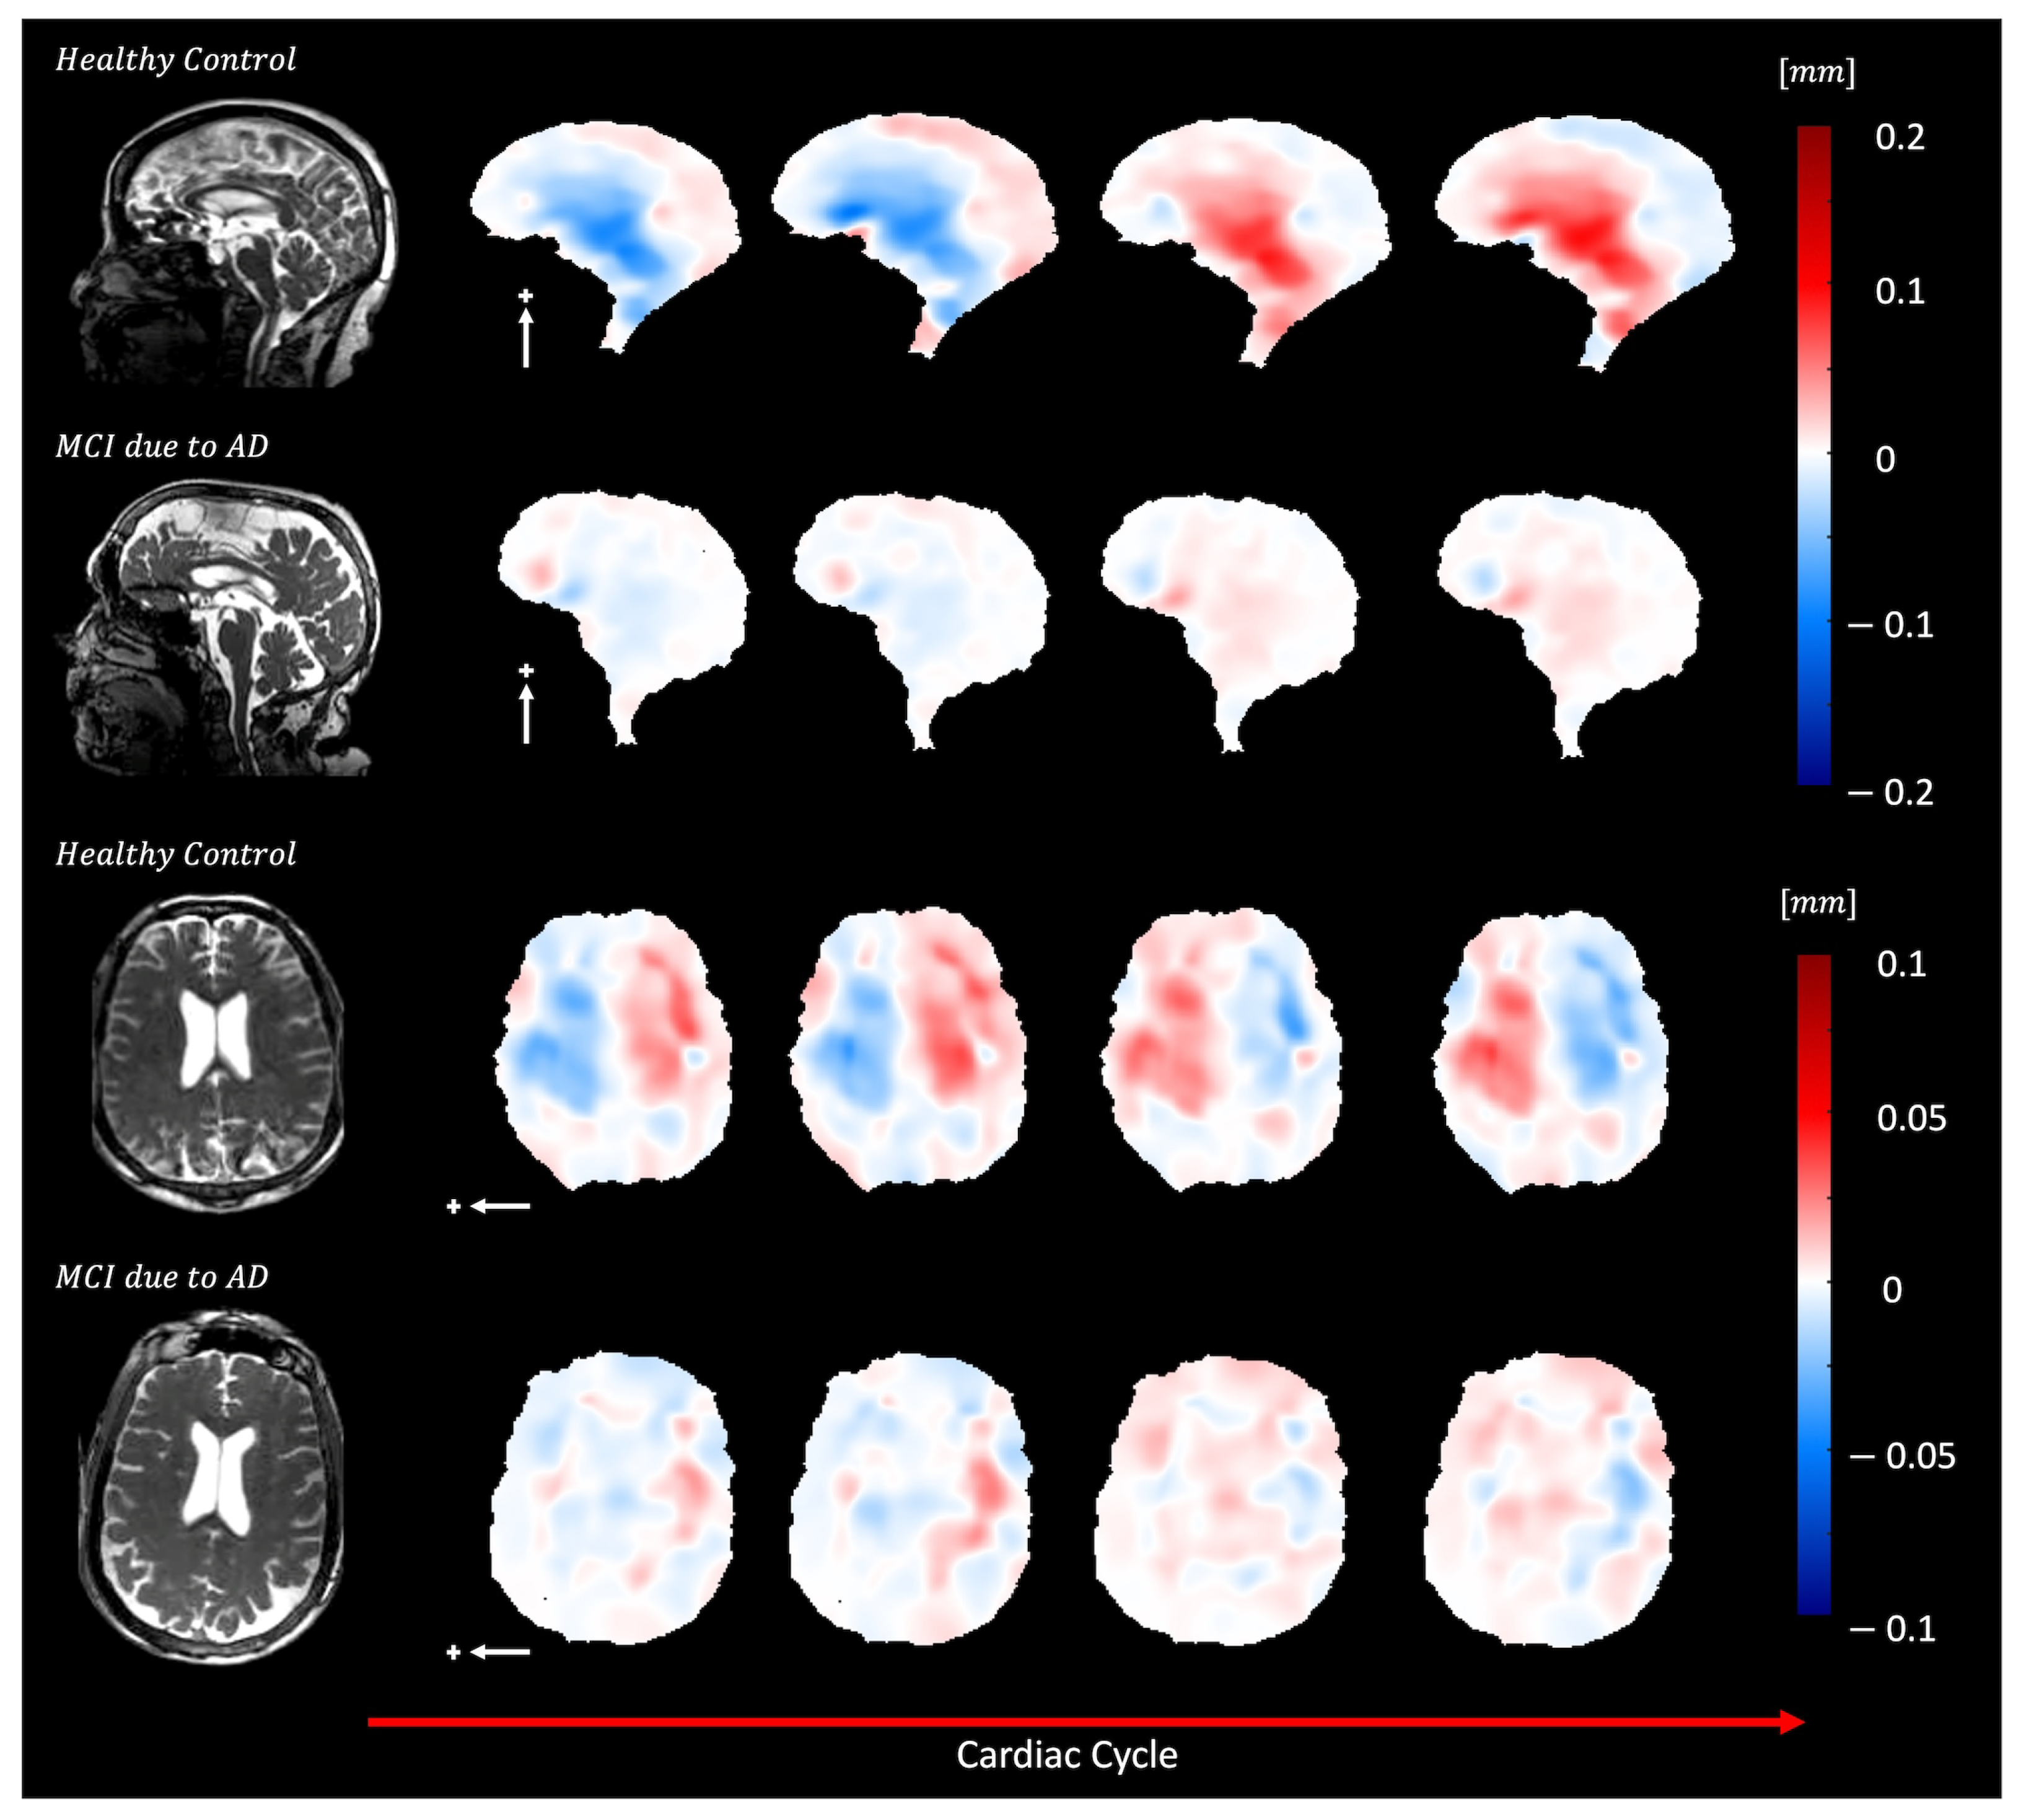

Figure 10 and Supplemental Video S10 show brain motion in a healthy control and a subject with mild cognitive impairment (MCI) due to Alzheimer’s disease (AD). In the AD participant, a diffuse reduction in brain bulk displacement is observed in both the sagittal and axial planes. Additionally, the displacement maps show a loss of symmetry and irregular motion of the lateral ventricles.

Figure 10. Depicts diffuse reduction in brain bulk displacement on both the sagittal (S/I direction, white arrow) and axial (L/R direction, white arrow) planes for elderly adults with MCI due to dementia (70-year-old female) compared to an elderly control (74-year-old female) plus sign represent the positive direction of motion. In addition, loss of symmetry and irregular lateral motion of the lateral ventricles are seen in the displacement maps.